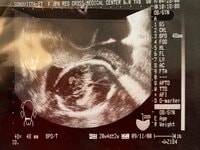

■妊娠中に受けた羊水検査

17日のブログでは21年前に出生前診断として受けたという「羊水検査」について回想。担当医師からは「『羊水を採取するとき、胎児の近くに針が刺さるので流産の危険が3%ありますがそれでもいいんですか』と聞かれた」といい、不妊治療の末に授かった子であったが「『それでもよい』と答えた」ことを明かしていた。